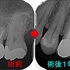

また治療するならリケージ(漏洩)が怖いので一度全ての人工物は外すと説明し治療スタート

1回目の治療で全てレジンを外し、隔壁+根管治療スタート

歯髄切断がしてありました。

2026 EEdental YOA (4).jpg

レントゲン

2026 EEdental YOA (3).jpg